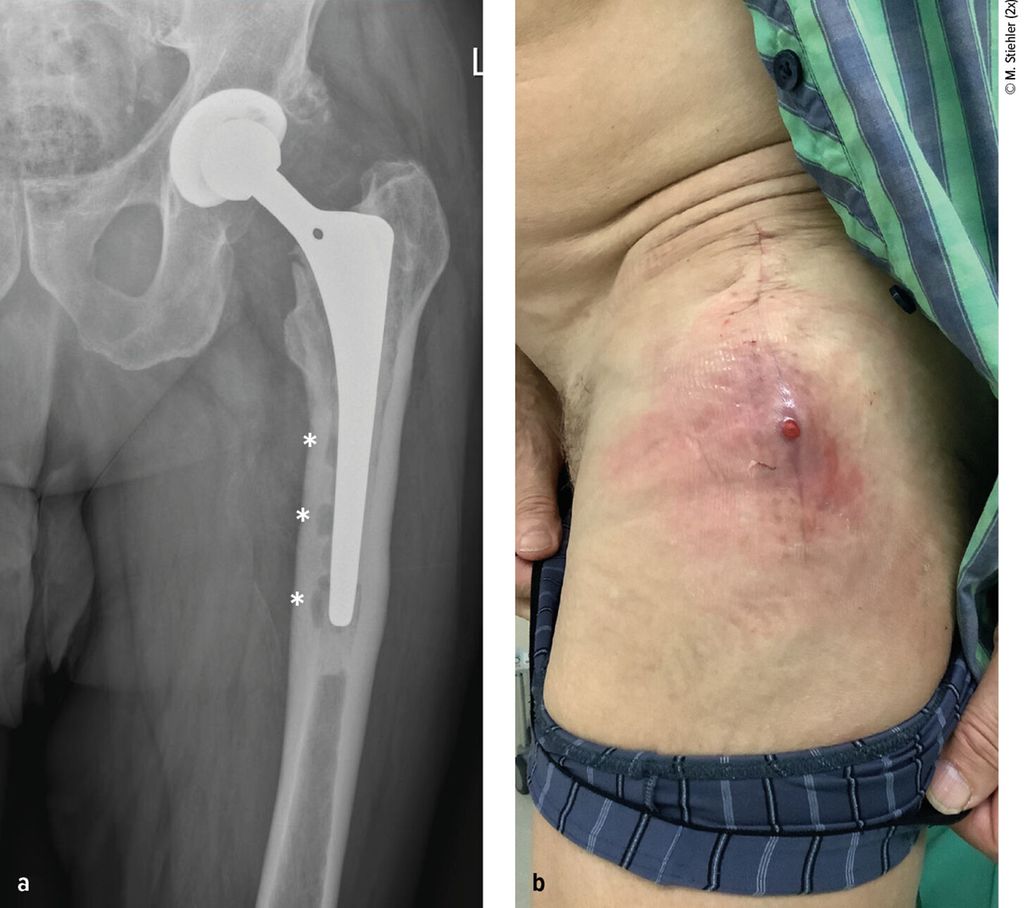

Anhand der klinischen Zeichen und der Symptomdauer unterscheidet man zwischen akuter und chronischer PPI. Die akute PPI ist durch eine kurze Symptomdauer (<3 Wochen) charakterisiert. Sie tritt entweder in der frühen (<4 Wochen) Phase nach endoprothetischem Gelenkersatz (akute postoperative PPI) oder aber verzögert (>4 Wochen, ggf. erst mehrere Jahre) nach Endoprothesenimplantation im Rahmen einer hämatogenen Streuung eines endoprothesenfernen Infektionsherdes (akute hämatogene PPI) auf. Typischerweise imponieren hier lokale Infektionszeichen wie Schmerzen, Schwellung, Rötung, Überwärmung oder eine prolongierte Wundsekretion (>7 Tage). Die Unterscheidung zwischen akuter und chronischer PPI basiert auf den Eigenschaften des bakteriellen Biofilms. Beim Vorliegen einer akuten PPI ist von einem unreifen bakteriellen Biofilm auf der Endoprothesenoberfläche auszugehen. Bei der chronischen PPI (>4 Wochen postoperativ) mit längerer Symptomdauer (>3 Wochen) liegt hingegen ein potenziell reifer Biofilm vor. Die klinischen Symptome sind in der Regel weniger ausgeprägt. Jedoch kann das Vorliegen einer kutanen Fistel oder von radiologischen Zeichen der Endoprothesenlockerung auf eine chronische Infektion hinweisen (z. B. Abb. 1).

Abb. 1: Patient mit chronischer Hüftendoprotheseninfektion. Radiologisch zeigen sich infektionsbedingte periprothetische Osteolysen (*, a) und klinisch imponiert eine kutane Fistel (b).